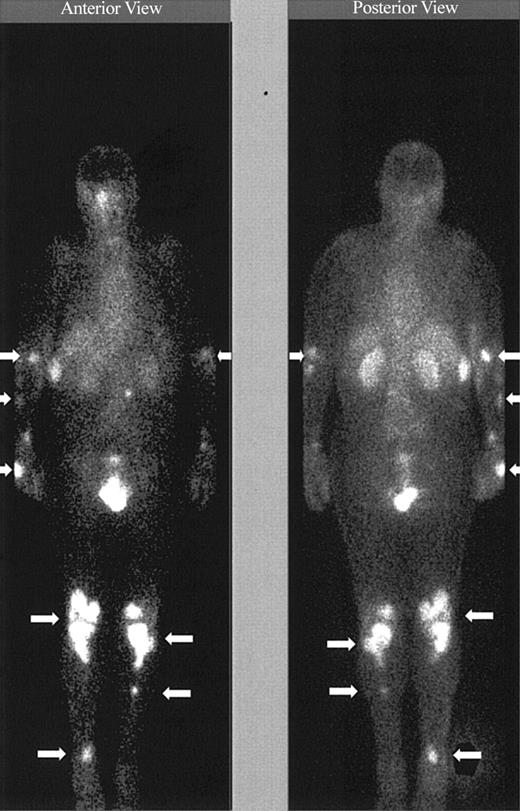

Imaging with Indium. Images obtained 20 minutes and 3 hours after infusion of the 111In-labeled DOTA-biotin demonstrated a rapid clearance of the blood pool radioactivity with early prominent kidney and bladder imaging reflecting the urinary route of excretion (Figure 3). Tumor sites were well delineated by 3 hours in all patients and were often visualized as early as 20 minutes after injection (Figure 3). Figure 4 demonstrates dramatic radiolocalization of the radionuclide in known nodal and extranodal tumor sites: subcutaneous nodules, skin, testes, and knees. The patient had serious knee pain, and magnetic resonance imaging confirmed that the unusual involvement around the knee area was consistent with non-Hodgkin lymphoma involvement of bone. Tumor localization of radioactivity persisted for the duration of the study. In 15 tumors evaluated, the estimated localization per gram of tumor was 0.01% to 0.04% of the injected dose.

Tumor targeting of known sites of disease. Images obtained 20 minutes, 3 hours, and 44 hours after the administration of 111In (5 mCi)/90Y (15 mCi/m2)–DOTA-biotin. Gamma camera wholebody scans of patient no. 1 (anterior views) obtained at 20 minutes, 3 hours, and 44 hours after infusion of 111In/90Y-DOTA-biotin. Arrows are showing radionuclide localization to known sites of tumor involvement.

Tumor targeting of known sites of disease. Image obtained 46 hours after the administration of 111In (5 mCi)/90Y (15 mCi/m2)–DOTA-biotin. Gamma camera whole-body scans of patient no. 3 (anterior view on left and posterior view on right) obtained 46 hours after infusion of 111In/90Y-DOTA-biotin. Arrows are showing radionuclide localization to known sites of tumor involvement.